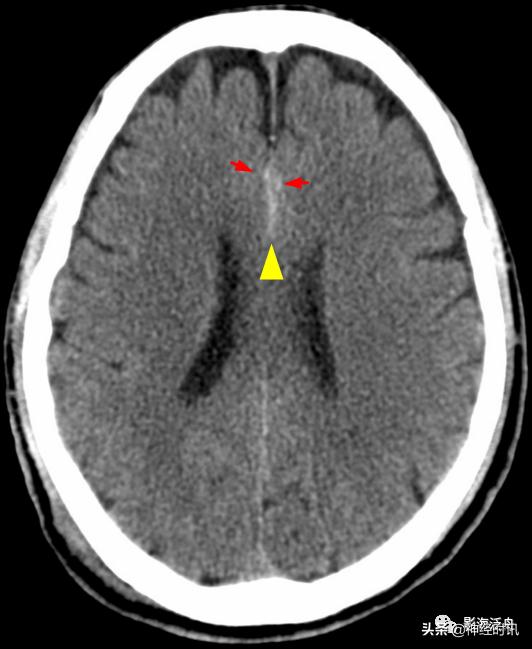

典型的大脑镰前部少量蛛血,血肿的边缘毛糙(红箭)且抵达胼胝体膝部的前缘(黄箭头)。4天后复查头颅CT平扫,相应部位少量蛛血基本吸收。

另一例表现类似的大脑镰前部少量蛛血,血肿的边缘总是有一种毛毛糙糙的感觉(红箭)。